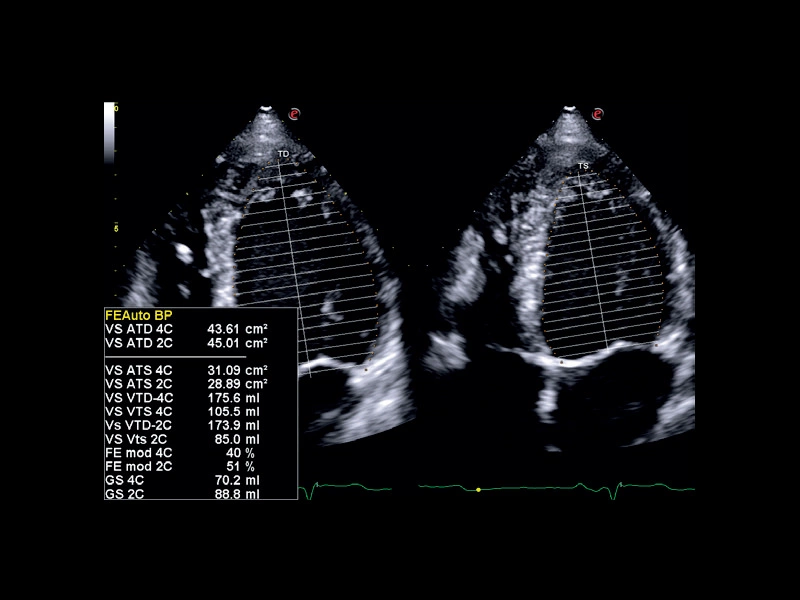

MyLab™C30 - FE

MyLab™C30 - FE